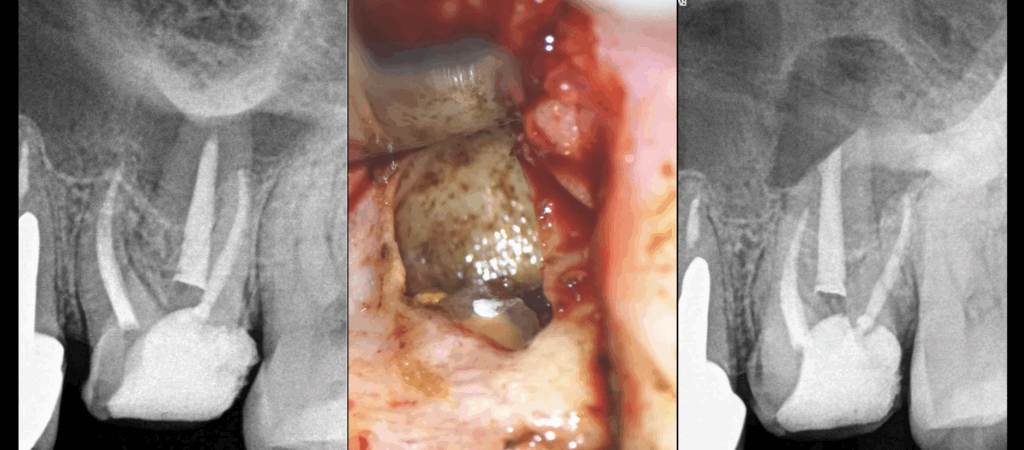

Endodontie par voie paralatine

Quand décider d’aborder la chirurgie endodontique par voie palatine ?

– 𝐋𝐨𝐫𝐬𝐪𝐮𝐞 𝐥𝐚 𝐝𝐢𝐬𝐭𝐚𝐧𝐜𝐞 𝐝𝐞𝐩𝐮𝐢𝐬 𝐥𝐚 𝐯𝐨𝐢𝐞 𝐯𝐞𝐬𝐭𝐢𝐛𝐮𝐥𝐚𝐢𝐫𝐞 𝐞𝐬𝐭 𝐭𝐫𝐨𝐩 𝐢𝐦𝐩𝐨𝐫𝐭𝐚𝐧𝐭𝐞

– 𝐋𝐨𝐫𝐬𝐪𝐮𝐞 𝐥𝐚 𝐝𝐢𝐬𝐭𝐚𝐧𝐜𝐞 𝐚𝐯𝐞𝐜 𝐥𝐚 𝐜𝐨𝐫𝐭𝐢𝐜𝐚𝐥𝐞 𝐩𝐚𝐥𝐚𝐭𝐢𝐧𝐞 𝐞𝐬𝐭 𝐚𝐬𝐬𝐞𝐳 𝐜𝐨𝐮𝐫𝐭𝐞

– 𝐋𝐨𝐫𝐬𝐪𝐮𝐞 𝐥’𝐚𝐫𝐭𝐞̀𝐫𝐞 𝐩𝐚𝐥𝐚𝐭𝐢𝐧𝐞 𝐦𝐚𝐣𝐞𝐮𝐫𝐞 (𝐚𝐧𝐜𝐢𝐞𝐧𝐧𝐞 𝐚𝐫𝐭𝐞̀𝐫𝐞 𝐠𝐫𝐚𝐧𝐝 𝐩𝐚𝐥𝐚𝐭𝐢𝐧) 𝐧𝐞 𝐩𝐚𝐬𝐬𝐞 𝐩𝐚𝐬 𝐞𝐧 𝐫𝐞𝐠𝐚𝐫𝐝 𝐝𝐞 𝐥’𝐚𝐩𝐞𝐱